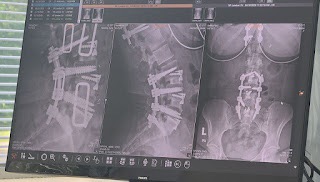

After four major back surgeries, I am fused T9-T12 in my thoracic & L4-S1 in my Lumbar. With rods and screws replacing the function of my spine, I was told that the mobility I had previously would never return. Immobility has not only caused me a lot of physical setbacks, but also feelings of worthlessness. I have felt like a burden on everyone around me due to my inability to do simple things, like put on my shoe, or pick up something off of the floor.